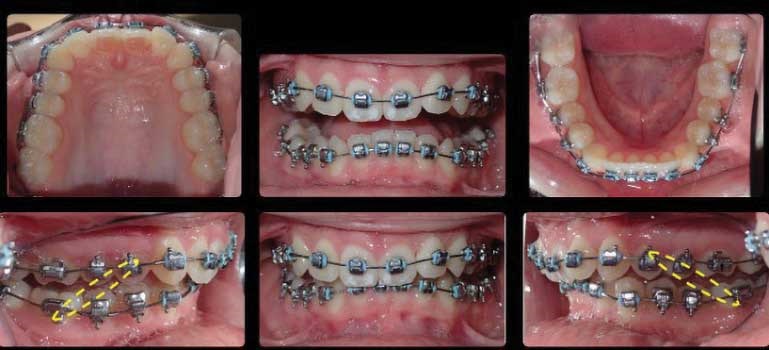

Case study

Figs. 1-3

Figs.9-11